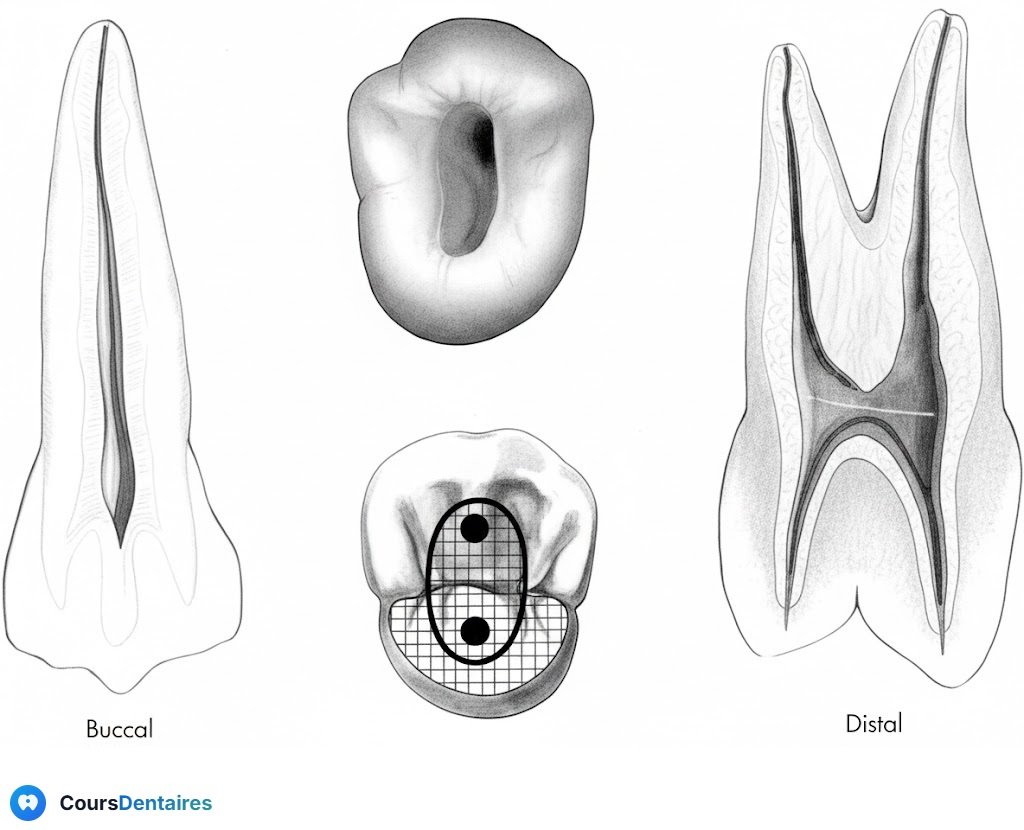

Molaires Mandibulaires

Première Molaire Mandibulaire

Forme : trapézoïdale, grande base mésiale, petite base distale

Position : déportée mésialement

Repérage des cornes :

Corne distale : intersection de la zone neutre (limitée par les sillons vestibulaire et lingual) et l’axe médian de la dent

Corne mésio-linguale : proximité de la fossette marginale mésiale

Corne mésio-vestibulaire : intersection de l’axe (passant par la corne ML et parallèle à la face mésiale) et la pointe cuspidienne MV

Précaution Technique

L’axe de la couronne diffère de celui des racines. Lors de l’approfondissement, tenez compte de l’inclinaison linguale pour éviter une perforation linguale.

Détection d’un Second Canal Distal

Test de la lime :

Si la lime est lâche dans un canal large et centré → un seul canal distal

Si la lime est serrée et s’oriente vers vestibulaire ou lingual → recherchez un second canal dans la direction opposée

Deuxième Molaire Mandibulaire

Simplification : les canaux mésiaux se rapprochent

Forme : cavité d’accès rectangulaire

Facilité : anatomie moins complexe que la première molaire